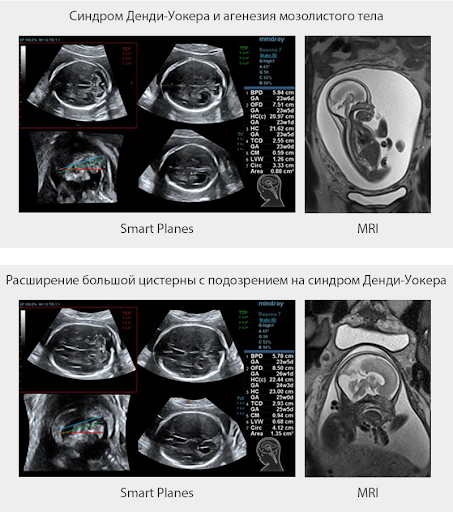

Smart Planes

Smart Planes — это удобный для пользователя инструмент, значительно повышающий эффективность сканирования за счет увеличения точности в сочетании с автоматизацией работы. Одного нажатия на клавишу достаточно, чтобы из 3D данных, полученных при сканировании мозга плода, немедленно получить стандартные плоскости сканирования ЦНС: MSP (медиальная сагиттальная плоскость), TCP (трансцеребральная плоскость), TTP (трансталамическая плоскость) и TVP (трансвентрикулярная плоскость), а также получаемые в них измерения (БПР, ОГ, ЛЗР, Поперечный Диаметр Мозжечка, Большая Цистерна и Ширина Бокового Желудочка)